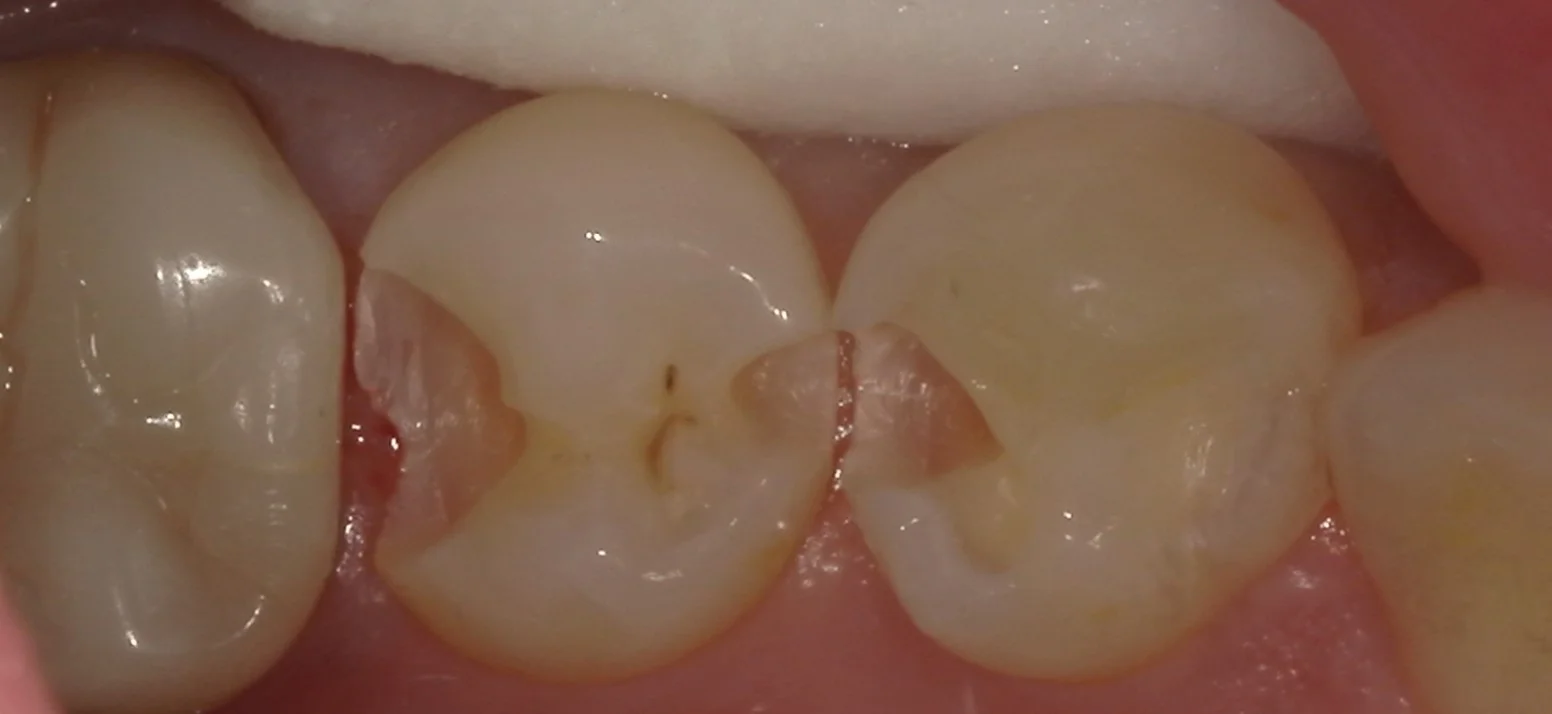

虫歯を取りきったのが、こちらです。

思ったよりも大きく中に入り込んでいましたね。

無事に神経とかは全く問題がない状態でしたので、成功率としては非常に高く出来るいいタイミングで治療に入れたと思います。